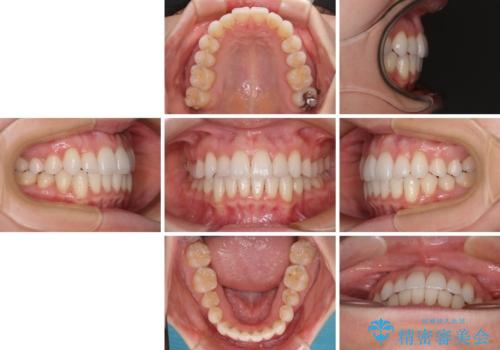

- 上下前歯のデコボコ、特に右上の八重歯を気にして来院された患者様です。

治療後半では悪阻によりマウスピースの装着時間が不十分となることもありましたが、それよりも前にしっかりと装着時間を守って治療を進めることができたため、特に気になるところなく治療を終えることができました。